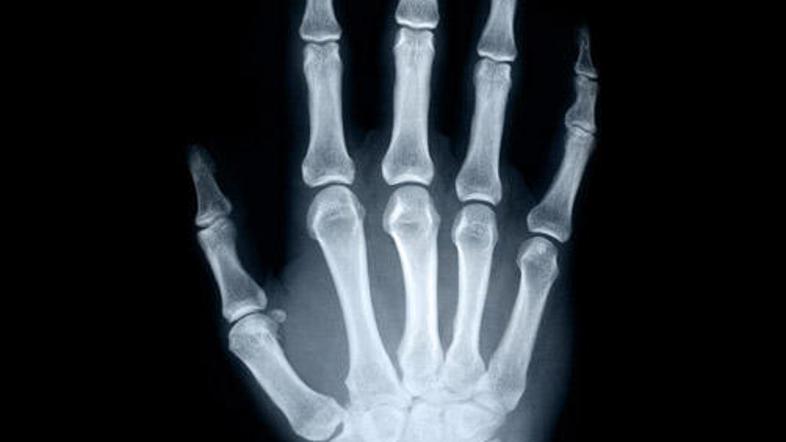

Večina projektov je usmerjenih k zdravljenju poškodb, ki so najpogostejše na bojišču. Posvečali so se predvsem izboljšavam presaditve živcev in žil, zdravljenju opeklin, ki ne bi puščalo brazgotin, samoobnavljanju tkiv, kože in celo kosti. Najuspešnejši so pri koži. V laboratoriju jim je uspelo vzgojiti novo kožo iz le nekaj celic kože pacienta. Še dolga pot pa jih čaka pri kosteh – v kliničnih poskusih jim je uspelo, da je kost zrasla v dveh letih za tri centimetre.